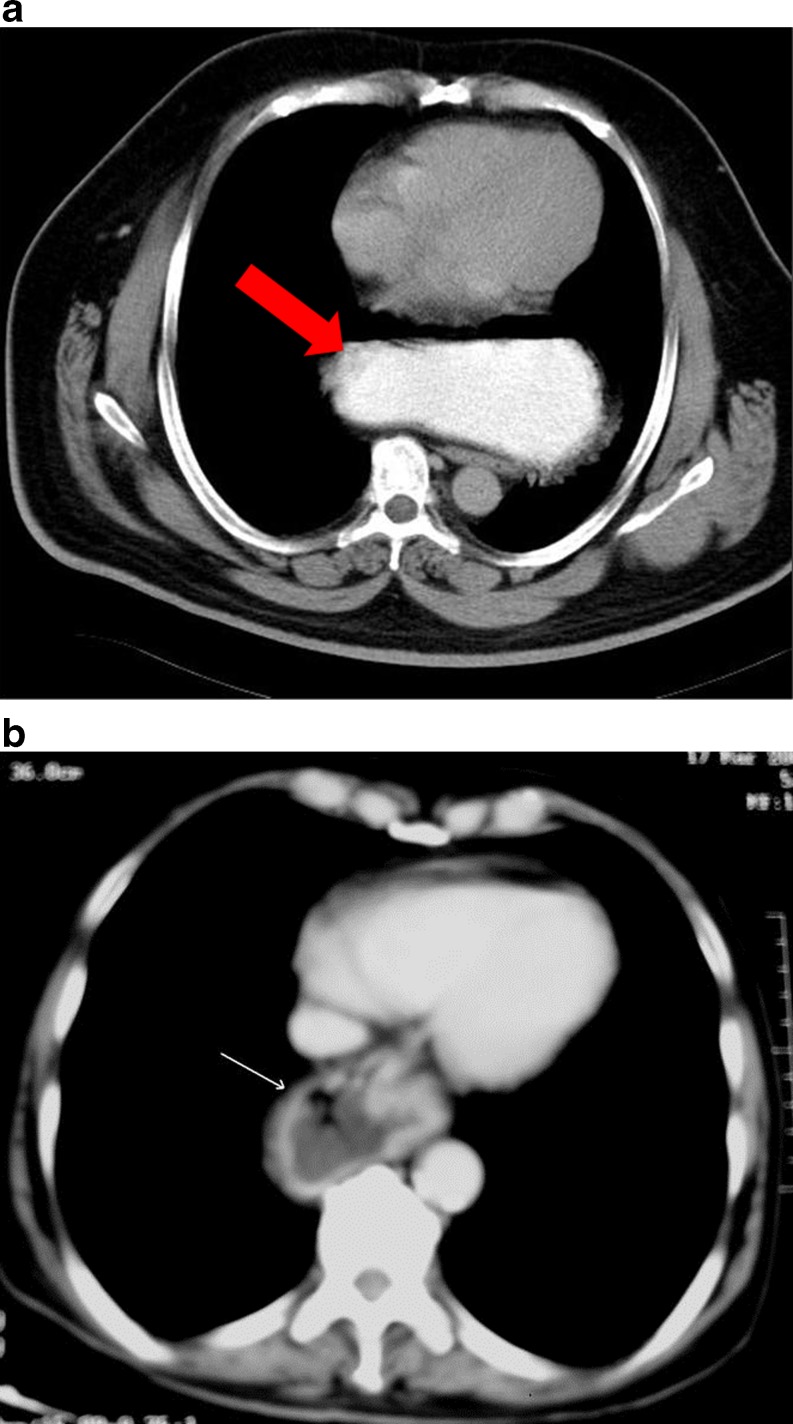

Morgagni’s Hernia

This is a rare form of congenital diaphragmatic hernia. It occurs through a potential defect in the right anterior medial part of the diaphragm posterior to the sternum. The defect is due to failure of fusion of the sternal and costal fibers of diaphragm. Liver, mesenteric fat and bowel can herniate through the defect (Fig. 9a-b) [28].

Fig. 9.

Morgagni hernia: Axial (a) and coronal (b) CT scan shows herniation of bowel loops with mesentery into the right hemithorax. Neck of the sac lies in the anterior paramedian location